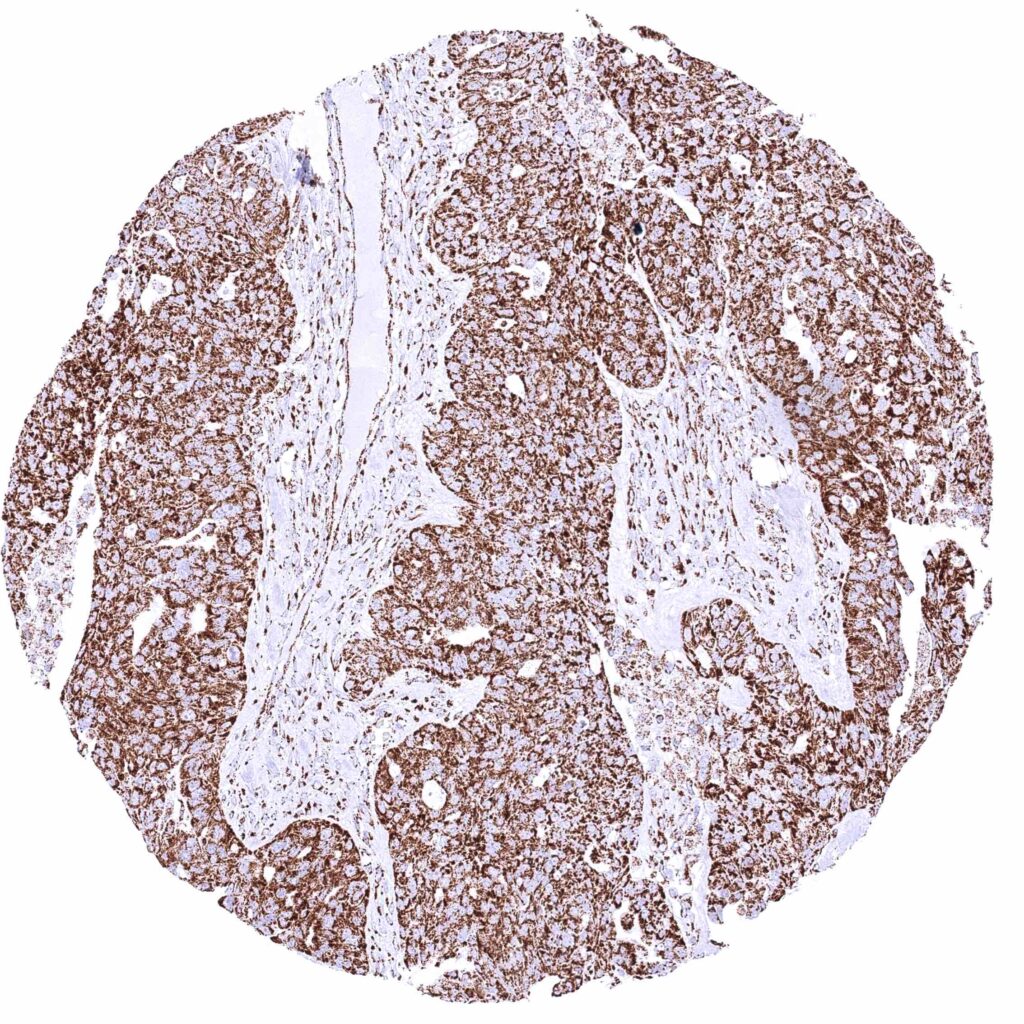

Testis – Seminoma with moderate cytoplasmic ATP5J immunostaining of tumor cells.